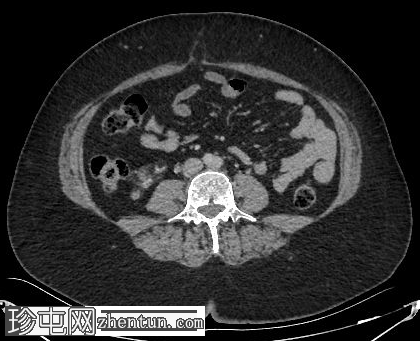

轴位

平扫

肝脏内可见多发边界清晰的脂肪结节状病变,最大病变位于肝脏VII段,直径15 mm

双肾可见多发脂肪肿块,右肾最大病变直径达45 mm,左肾最大病变直径20 mm

心肌脂肪组织

椎体可见小的硬化性骨病变

胆囊腔内可见多发结石,诊断为胆石症

可见小的脐疝,内含腹膜前脂肪

肾血管平滑肌脂肪瘤是结节性硬化症最常见的腹部表现,通常为多发性、双侧性,且体积大于散发性病变。血管平滑肌脂肪瘤。肝脏血管平滑肌脂肪瘤虽然不常见,但却是公认的肾外表现,其影像学特征与肾脏血管平滑肌脂肪瘤相似,包括CT扫描可见肉眼可见的脂肪,这使得诊断成为可能,且无需侵入性检查。

肾脏和肝脏中富含脂肪的血管平滑肌脂肪瘤可能仅有轻微或无明显的对比增强,仅表现为衰减值的轻微升高,反映血管和间质成分的增强。这些病灶内肉眼可见的脂肪具有高度特异性,有助于将血管平滑肌脂肪瘤与其他肾脏和肝脏肿瘤区分开来。